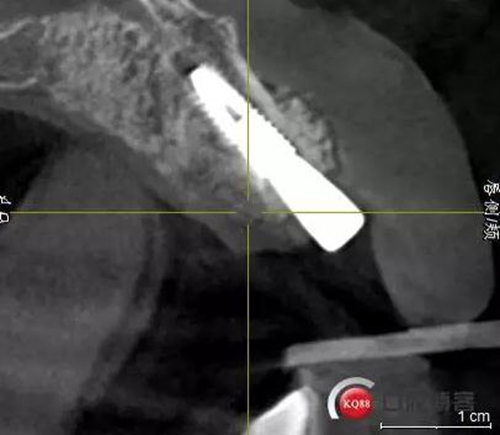

術(shù)后CBCT